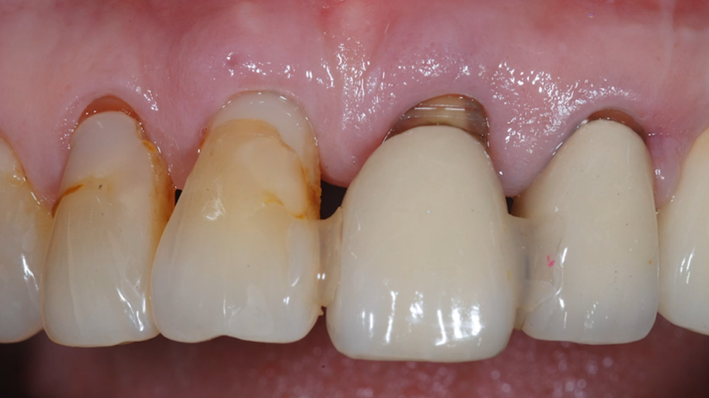

Clinical case: : R2GATE guided surgery & immediate implant placement

- Courtesy of Dr. Kwang Bum Park, Korea -

Dr. Kwang Bum Park, immediate loading, digital guided surgery, digital ONE-DAY implant, maxillary anterior, #21, guided surgery, immediate loading, AnyRidge, R2GATE, Mega ISQ, MEG Torq, R2GATE Full Surgical Kit

implant system, R2GATE Guide, R2GATE full surgical kit, Mega ISQ